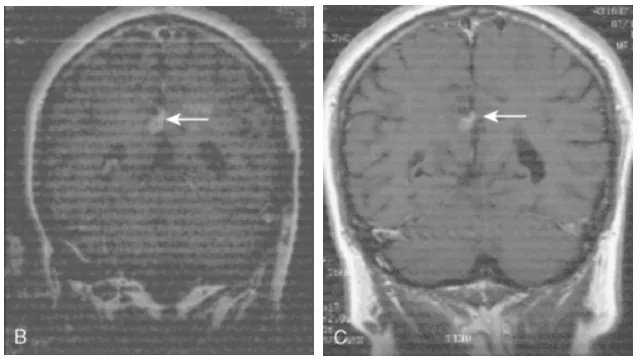

世界神经外科联合会(WFNS)颅底手术委员会前主席Sebastien Froelich教授(塞巴斯蒂安·福洛里希教授,福教授)在手术中采用了内镜辅助下右额下入路肿瘤全切术,为她实施了精准的手术治疗。该手术实现了肿瘤的完全切除,达到了辛普森II级标准。术后,患者的视觉功能得到了显着改善,同时嗅觉功能也保持了完好,没有出现脑嵴液渗漏的情况。

术前及术后磁共振成像。术前preop(A)和术后Postop(C)显示肿瘤完全切除。